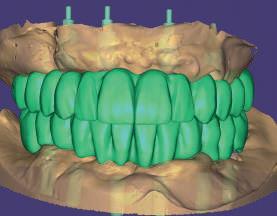

60 year old male patient visits the clinic with the desire to restore his oral health in a fully comprehensive manner.

Upon physical examination we found absence of teeth in both jaws and remaining teeth with recurrent caries, advanced periodontal disease and mobility; with a poor prognosis for function and aesthetics. We proceeded to take all the preparatory records such as: scans, photographs, x-rays, tomography and other diagnostic elements for the planning of rehabilitation by means of dental implants.

According to the prosthetic planning in the co diagnostix software, it is decided to extract the remaining upper teeth, leaving two teeth temporarily for stabilisation of the surgical guide and as a reference for the immediate scanning after the placement of 4 single-stage implants (Fixo. Oxy. Italy).

In the lower part the extraction of the remaining teeth is planned and the immediate placement of 6 implants (dynamic hex. Cortex . Israel) and and the immediate placement of Multi Units Abutments (MUA. DAS. Dynamic Abutment Solutions. Spain). However, when planning for the lower implants at the same level, there is a collision of the sleeves with the bone that prevents the placement of the implants at the same level (fig. 6), so the offset of the anterior implants is modified to ensure the correct position in the guide, avoiding interference with the bone and placing the implants at the same level (fig. 7).